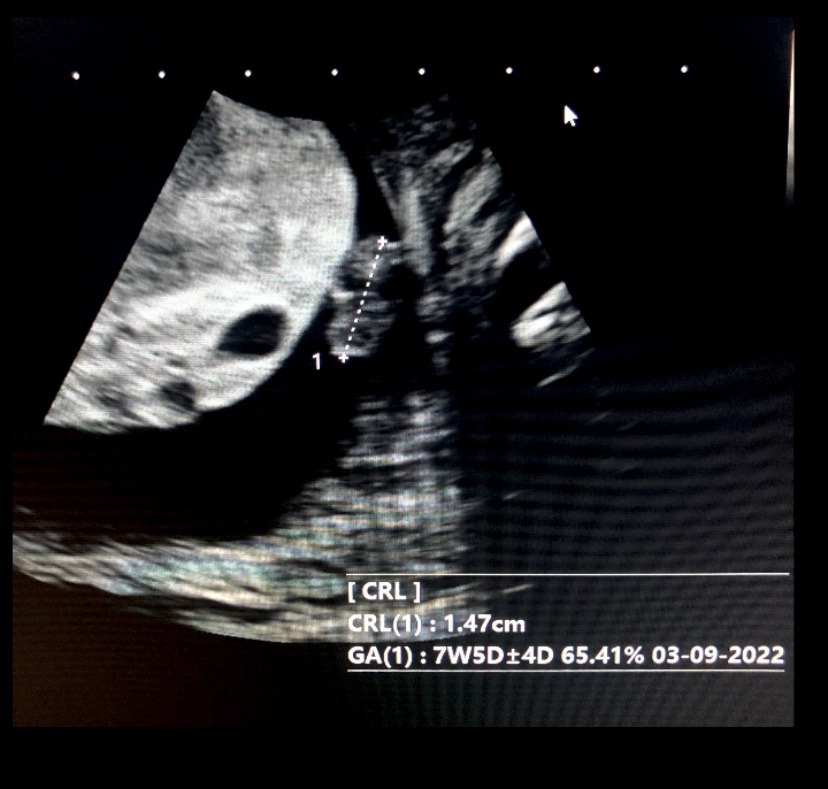

Case 2

Incomplete moles have Triploid genotype (69XXY, 69XXX) usually contains fetal/embryonic tissue/cells. hCg usually <100,000

<5% become invasive